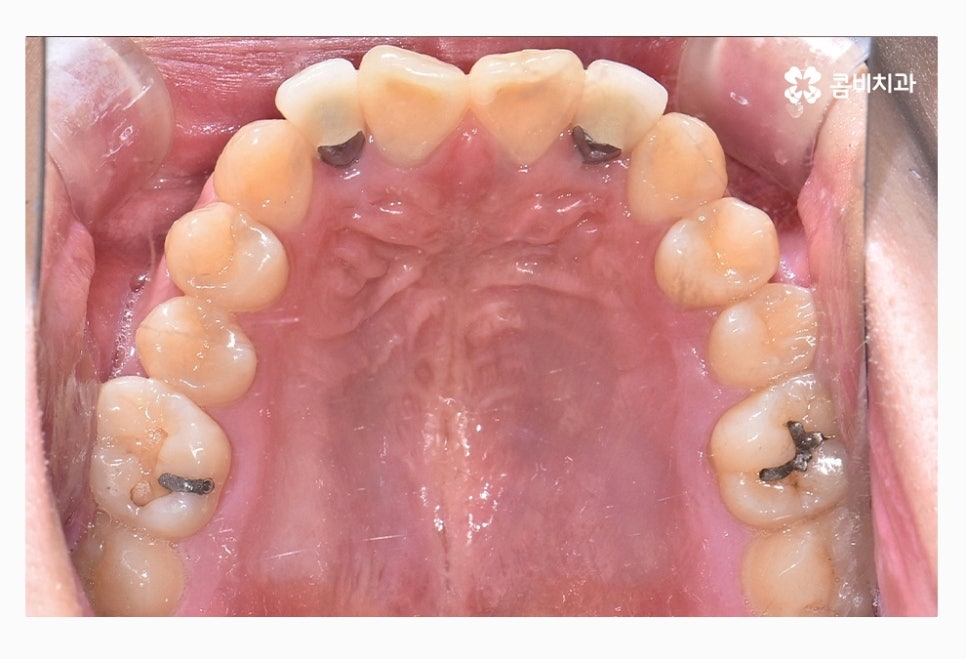

좌측 사진이 윗니이며 우측 사진이 아랫니인데

윗니가 치열이 좀 더 삐뚤다는 것을 알 수 있어요.

위 사진을 다시 한번 자세히 보면 윗니는 치아의 안쪽에

교정 장치가 부착이 되어 있는 모습이며

아랫니는 일반적인 교정 방법으로 장치가 부착되어 있어요.